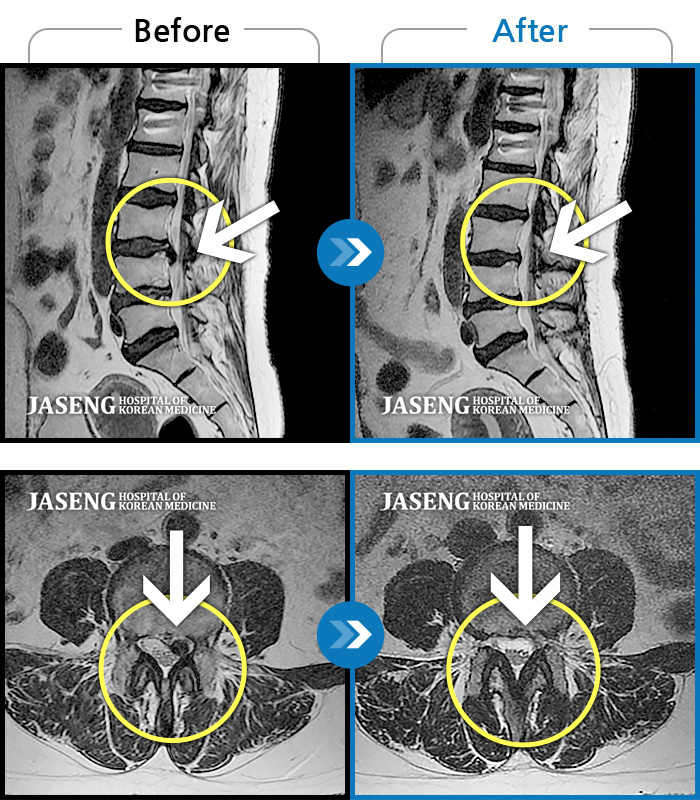

허리디스크

일산 · 김태용 원장

허리와 좌측 다리가 당겨 보행이 불가능했다.

촬영시기

2020.02.10 ~ 2021.02.22

2021.02.26